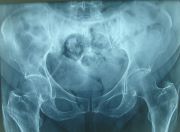

1. Osteoarthritis of both hips but is more severe on the right side.

Treatment: Total hip arthroplasty in a 73-year-old female

I. Anteroposterior x-ray of the pelvis and hips II. One-month post-surgery, anteroposterior x-ray pelvis shows the THA III. One-month post-surgery, lateral x-ray of the right hip showing the exact position of the stem in the femur